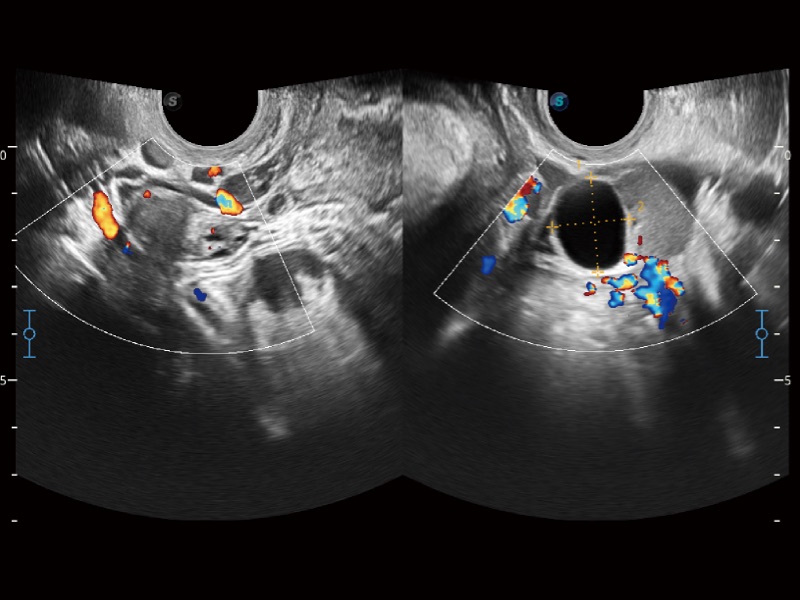

妇产科应用

三维光影成像技术采用新型的渲染方式,增强边缘信息,使得轮显示清晰完整,为临床提供丰富、直观的三维结构,提供临床诊断准确性。